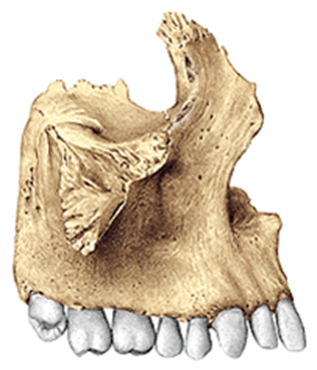

Antes de visualizar las radiografias observemos las estructuras oseas que conforman el viscero craneo, algunas de esas estructuras se obervan en las radiografias dentales anteriores y posteriores.

Huesos que conforman el viscero craneo

Vista lateral del maxilar superior. Si quieres profundizar en el tema te dejo un enlace https://anatomiatopografica.com/huesos/hueso-maxilar-superior/